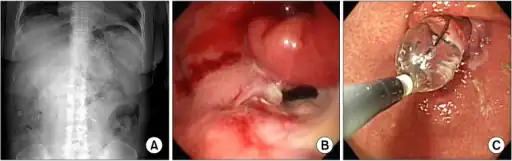

| X-ray showing a large amount of food in the stomach due to severe gastroparesis[1] | |

-

a-c)Radiologic and endoscopic finding of delayed gastric emptying -